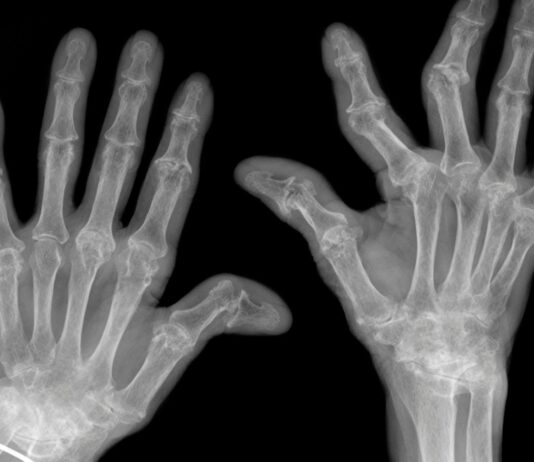

Artrosi: quanto aiuta davvero l’esercizio fisico

Un revisione sistematica coordinata dalla Bochum University of Applied Sciences, in Germania, e del Copenhagen University Hospital Bispebjerg Frederiksberg di Copenhagen, in...